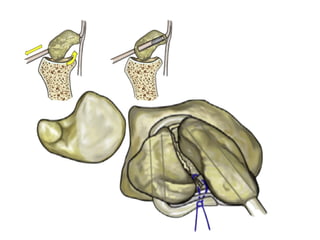

This presentation discusses various topics related to the wrist including static scapholunate ligament dissociation, dorsal ganglion cysts originating from the dorsal capsulolunate septum, treatment of scaphoid pseudarthrosis using a bone graft from the distal radius placed under the extensor tendons, and proximal pole scaphoid pseudarthrosis treated with capitolunate arthrodesis. It also thanks attendees and provides instructions for accessing the presentation online.